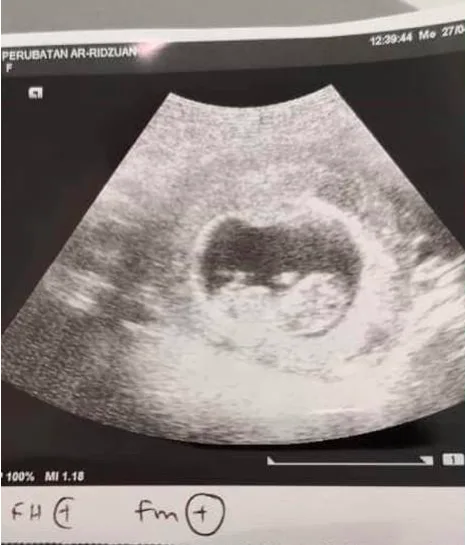

Hamil 10 Minggu

Menurut Jamal, isterinya kini disahkan hamil 10 minggu dan mereka sudah berjumpa doktor bagi tujuan pemeriksaan dan melakukan ujian imbasan apabila isterinya mengalami alahan serta tidak datang bulan.

“Rezeki teman (saya). Udah (sudah) 10 minggu. Aduii,”

“Pengesahan diterima dua hari lalu, tapi belum nampak jantina,” katanya menerusi WhatsApp.